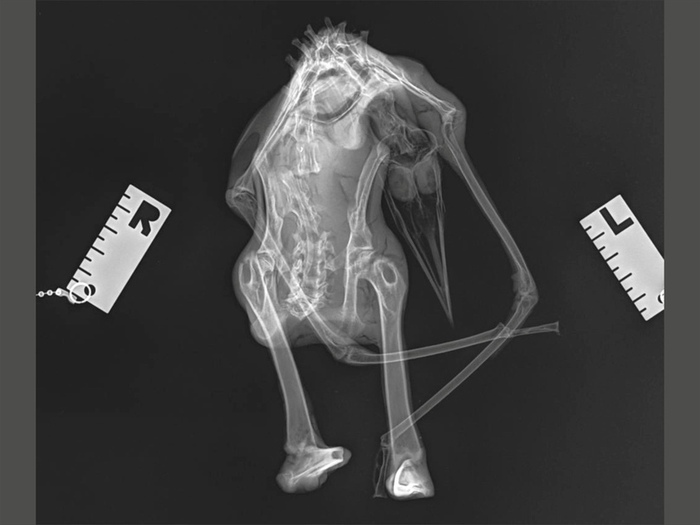

Был сделан рентген. В двух проекциях.

Рентген показал как особенности строения дриопингвина, так и вероятную причину его смерти — сломанный позвоночник. Вероятно, существо прятало тело жирное в утёсах, сорвалось вниз, разбилось и было естественным образом мумифицировано, а потом на этом месте был построен метрополитен.